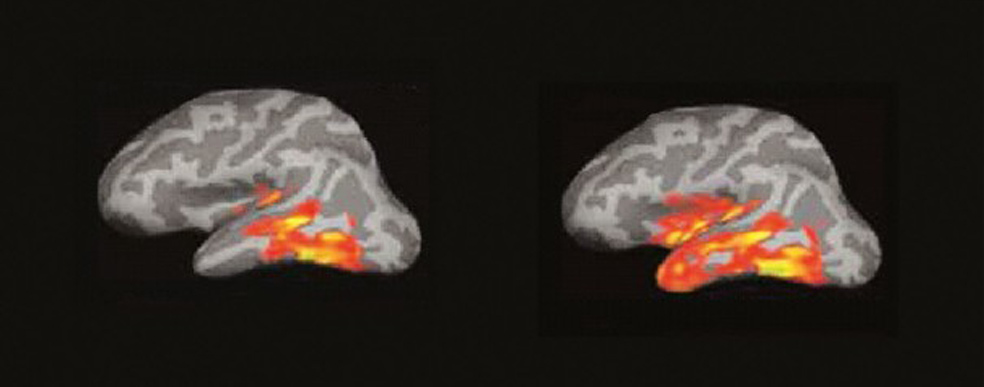

El cerebro del lector: un incendio de ideas

La imagen por resonancia magnética del cerebro de alguien que lee muestra algo parecido a un incendio forestal en un día de viento. Las pavesas vuelan y prenden nuevos conatos en diferentes zonas…